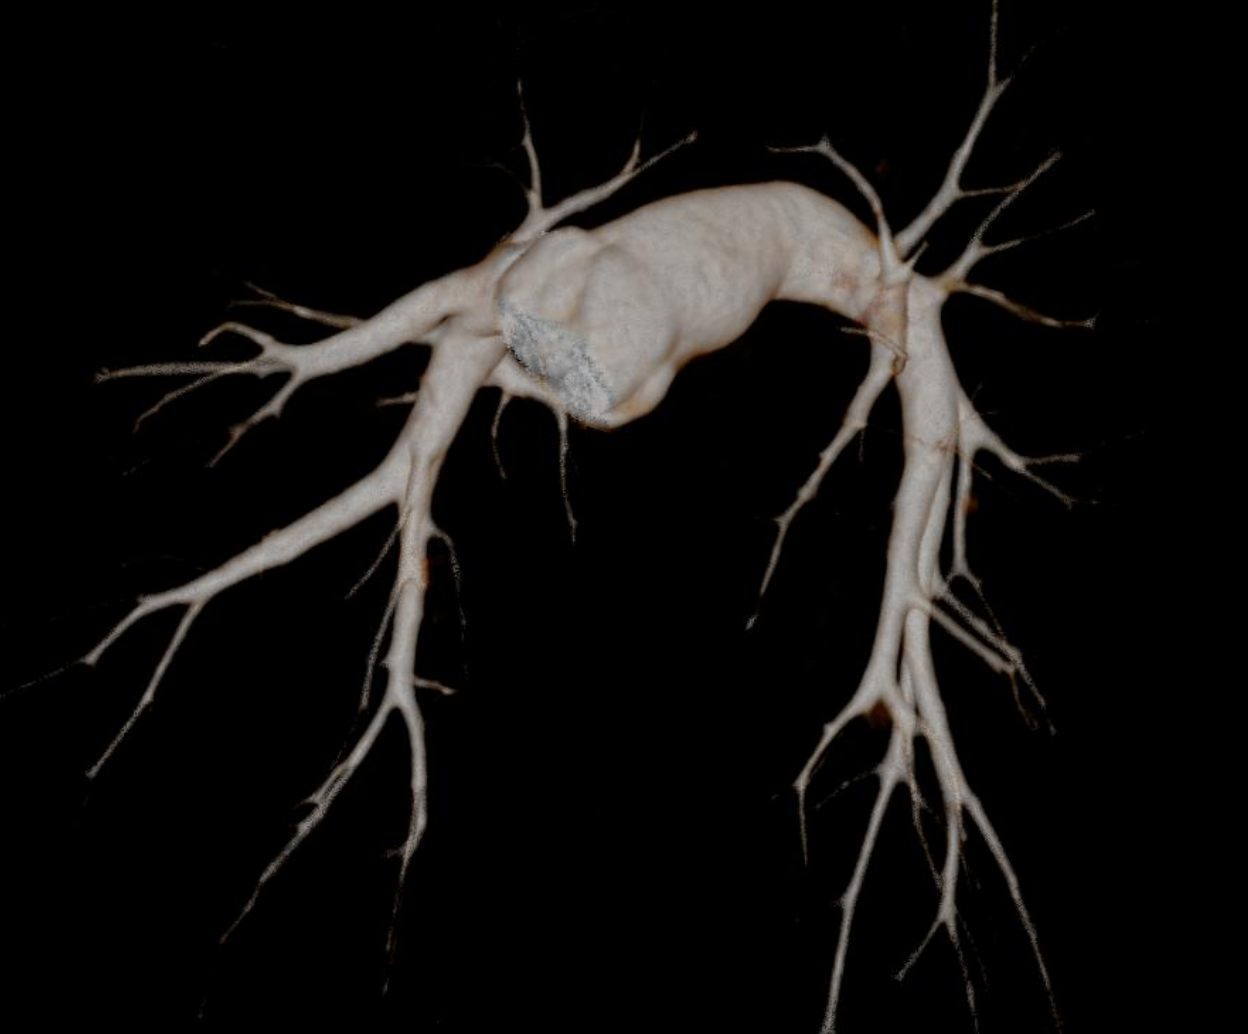

Hệ thống CT tiên tiến này sở hữu tốc độ quay siêu nhanh 0,286 giây, bóng tia X công suất 7,5 MHU (hiệu dụng lên đến 27,1 MHU) cùng detector độ rộng 40 mm. Nhờ các công nghệ hiện đại, hiệu suất chụp tim vượt trội được nâng lên một chuẩn mực mới, mang lại hình ảnh tim mạch chính xác và ổn định. Thiết bị tích hợp nền tảng AI toàn diện, bao phủ toàn bộ quy trình từ định vị bệnh nhân, quét, kiểm soát liều, giảm nhiễu và triệt tiêu artefact đến hậu xử lý hình ảnh và hỗ trợ chẩn đoán, đảm bảo độ chính xác vượt trội ngay cả trong những tình huống lâm sàng phức tạp nhất.